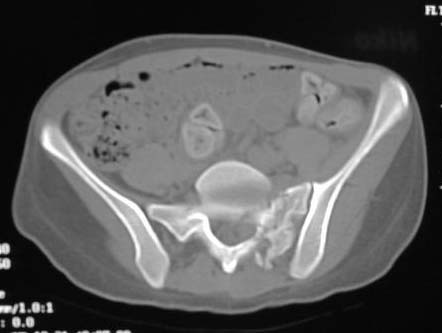

An example of our current approach to similar injuries - A 26 y.o. male admitted to us Aug 23, 2001 6 weeks after injury (compression by a wheel of a truck).

An external fixator was applied and gradual reduction was started - lateral traction to mobilize sacral fracture and then the hemipelvis was moved downward. Then lateral compression was performed. Yesterday iliosacral screws was inserted.

The last couple of images are skewed, they were made in OR and patient was not properly positioned.